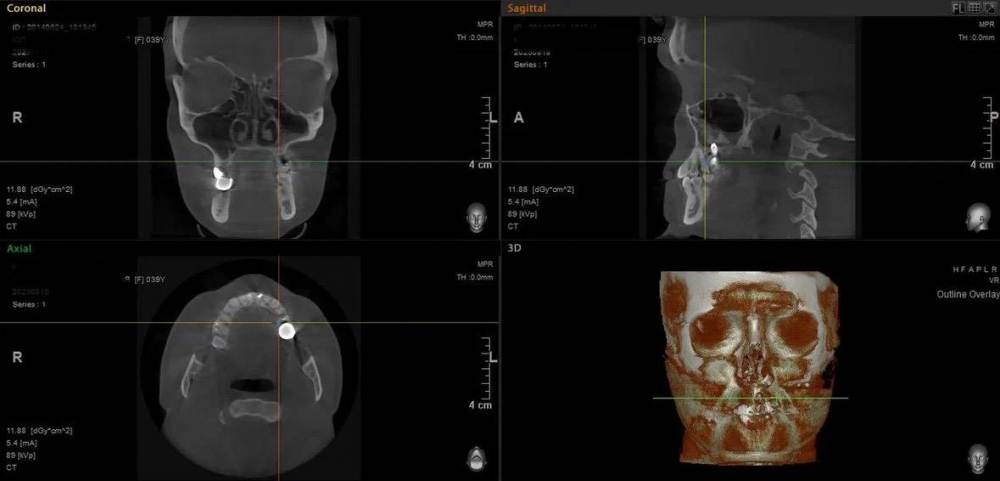

Mitt Опубликовано 29 октября, 2023 Поделиться Опубликовано 29 октября, 2023 (изменено) Здравствуйте. Ж., 39 лет. Так получилось, что мне нужно решить, что делать с имплантатом на месте верхней шестерки. А тк я не обладаю необходимой компетенцией, очень нуждаюсь в подсказках специалистов. Дано: 1. 2014-2015 гг - удаление зуба, синус лифтинг, имплантация с пластикой мягких тканей, установка коронки. 2. 2015 - 2019 гг - проблема контактов с рядом находящимися пятым и седьмым зубами, воспаление десны вокруг 5, имплантант, 7. Решалось путем композитных «накладок» на 5 и 7 зубы. 3. 2019 - 2023 гг - пластика мягких тканей, удаление 7 зуба с подсыпкой графта, еще штуки 3 или 4 пластики, включая вестибулопластику, временная коронка. 4. 2023 г - установка новой постоянной коронки, 5 месяцев тишины, с августа гной в районе имплантата (десна спокойна). Проблемы общие для всех временных периодов - тандем с пазухой и периодические ближе к постоянным боли разной интенсивности и локации (пазуха, 7 зуб, место от 7 зуба, стенка носа, кость), мне сложно лоцировать( Мне нужно выбрать, что делать дальше: попробовать почистить имплантат, или уже отпустить=удалить. Вариант почистить и еще сделать пластику пока не рассматриваю, тк после стольких пластик частичная парастезия неба. Может быть, кто-то подскажет, к какому решению в итоге прийти.. P.s. Я не знаю , какие скрины кт нужны( кт 08.2023 Изменено 29 октября, 2023 пользователем Mitt Ссылка на комментарий